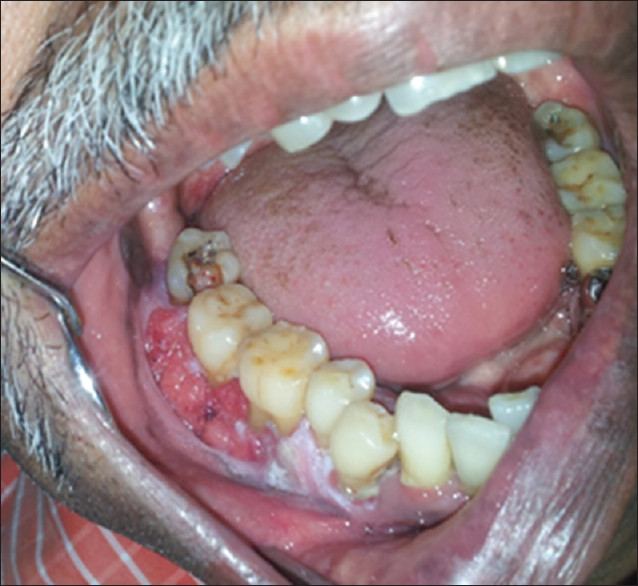

Smoker’s Melanosis

Smoker’s melanosis is increased tissue pigmentation, or darkening, due to irritation from tobacco smoke. Typically this pigmentation occurs on the gingiva (gums) of the upper and lower front teeth. The amount of pigmentation increases with greater tobacco use, and is more common in females; it occurs in 5.0 – 22% of cigarette and pipe smokers. There is no treatment for smoker’s melanosis; however, tissues typically return to normal color in six to 36 months after quitting smoking.

Periodontal Disease

The evidence is overwhelming that smoking contributes to periodontal disease (see Right) and that continued smoking results in a reduced response to periodontal treatment. There is a greater amount of bone loss around teeth in smokers and individuals who smoke are more likely to lose teeth than nonsmokers. It is reported that more than half of advanced gum disease can be linked to tobacco use.

Oral CancerUse of tobacco products is clearly linked to development of oral cancer (see Below). Oral cancers are found primarily in the floor of the mouth (under the tongue), the sides and underside of the tongue, and the soft palate (the back part of the roof of the mouth). The topic of oral cancer in discussed in a separate Patient Information sheet. The most important key to surviving oral cancer is early detection. The importance of your dentist performing a thorough soft tissue examination cannot be overemphasized. The tissue changes in early cancer can be subtle and it is essential for your dentist to perform a through soft tissue examination to detect cancer at an early stage. He or she may want to take a sample of these tissues (biopsy) for diagnosis, or refer you for this procedure. This is the only way to make a diagnosis of oral cancer, and biopsy can also help in determining your long-term outlook.